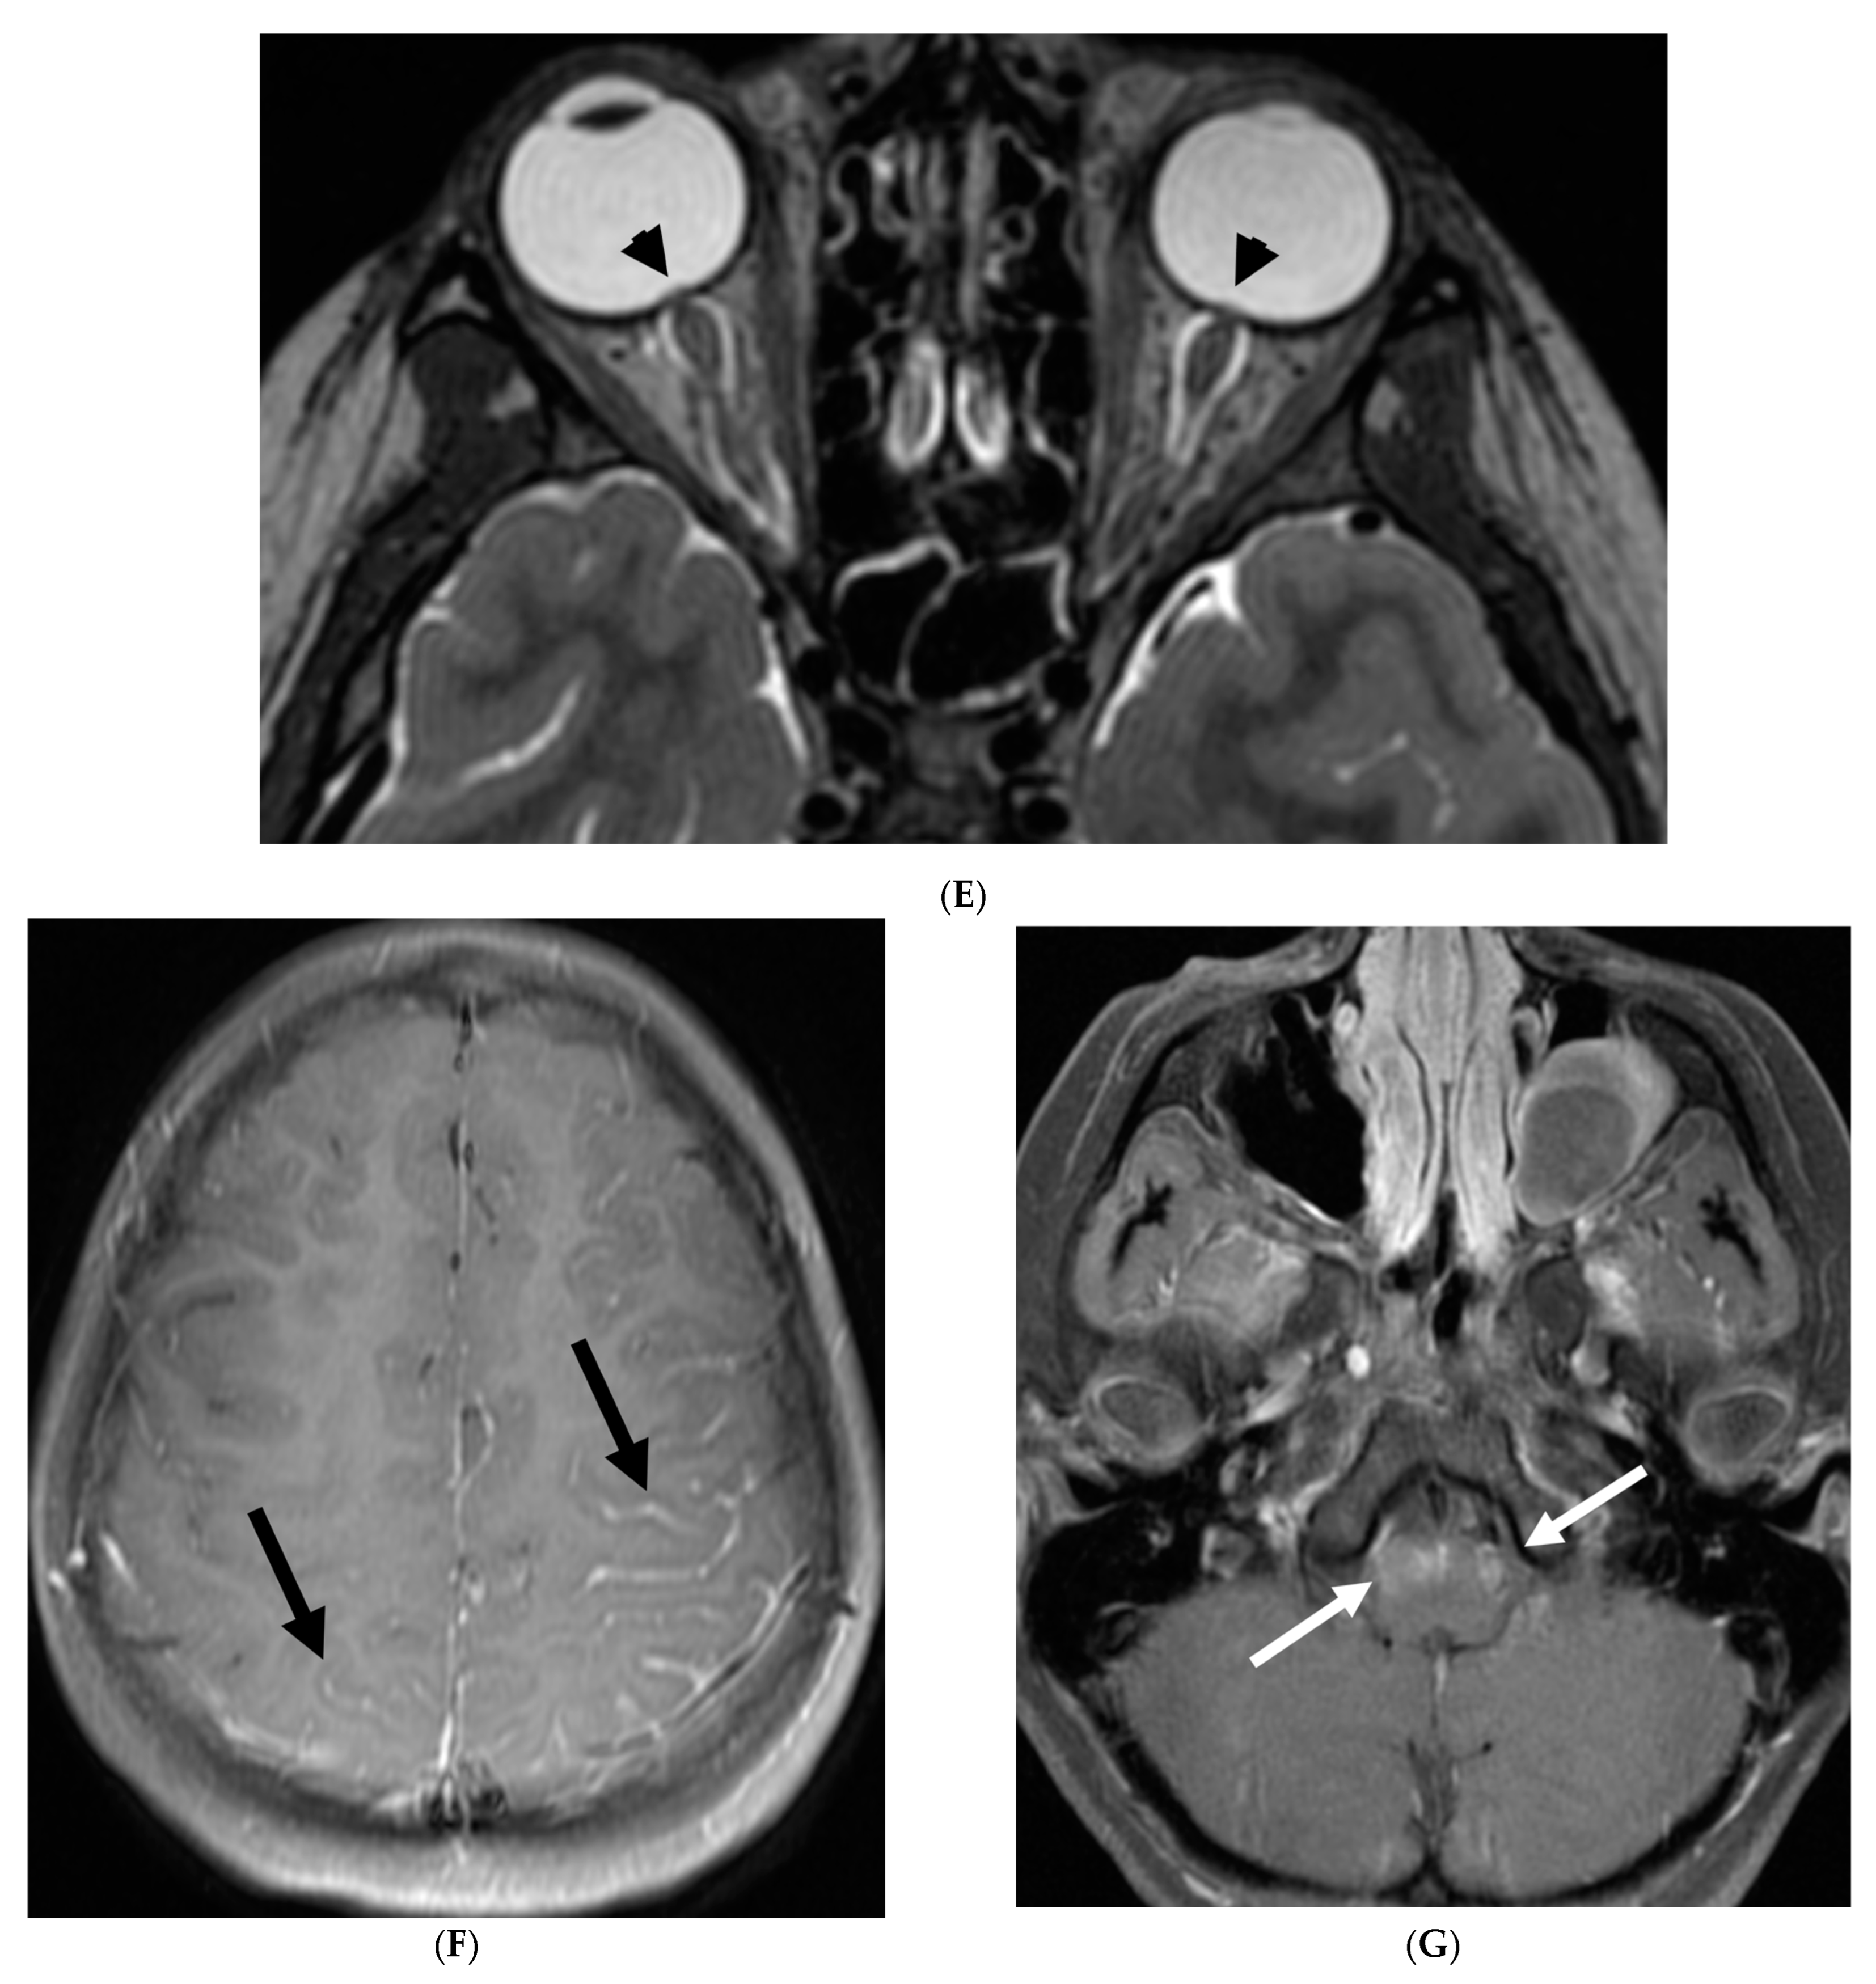

Figure 21.

Sagittal T2 (A,B), axial FLAIR (C), axial T2 cervical spine (D) at the level of C7 vertebral body and Axial T2 orbits (E): 12-year-old girl presented with right focal motor seizure and left temporal lobe slowing on electroencephalogram (EEG). Right eye vision loss and irritability. Ill-defined areas of signal abnormalities are identified within the RIGHT mesial temporal lobe and bilateral medulla (white arrows). FLAIR hyperintensity is identified on the left central sulcus (black arrow). Small focus of signal abnormality is seen on the right side of the cord at the 7th cervical vertebra (C7) (dashed arrow). There is also bilateral papilledema (arrowheads). Post contrast axial T1 (F,G), axial T1 orbits (H) and axial T1 cervical spine at C7 (I): Asymmetric LME (black arrows) predominantly involving the left cerebral hemisphere, with minimal right parietal involvement is seen. Ill-defined enhancement in the right mesial temporal lobe, and right greater than left medulla (white arrows) corresponds to the signal abnormality. There is right greater than left, optic nerve enhancement (curved arrow). Single small enhancing lesion in the spinal cord on the right at the level of C7 corresponds to the signal abnormality (dashed arrow). Features favor a demyelinating process. MOG antibodies were positive at 1:20 in keeping with Myelin oligodendrocyte glycoprotein (MOG) antibody disease (MOGAD).